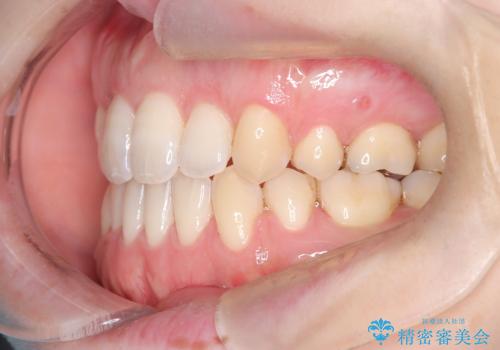

治療後は、前歯の位置や噛み合わせが整い、見た目も機能面も大きく改善されました。きれいな歯並びを得ることができ、患者様にも非常に満足していただけました。

抜歯によって確保したスペースを活用し、効率的に歯列を整えました。前歯のガタガタと八重歯が解消され、自然で美しい仕上がりを実現しました。